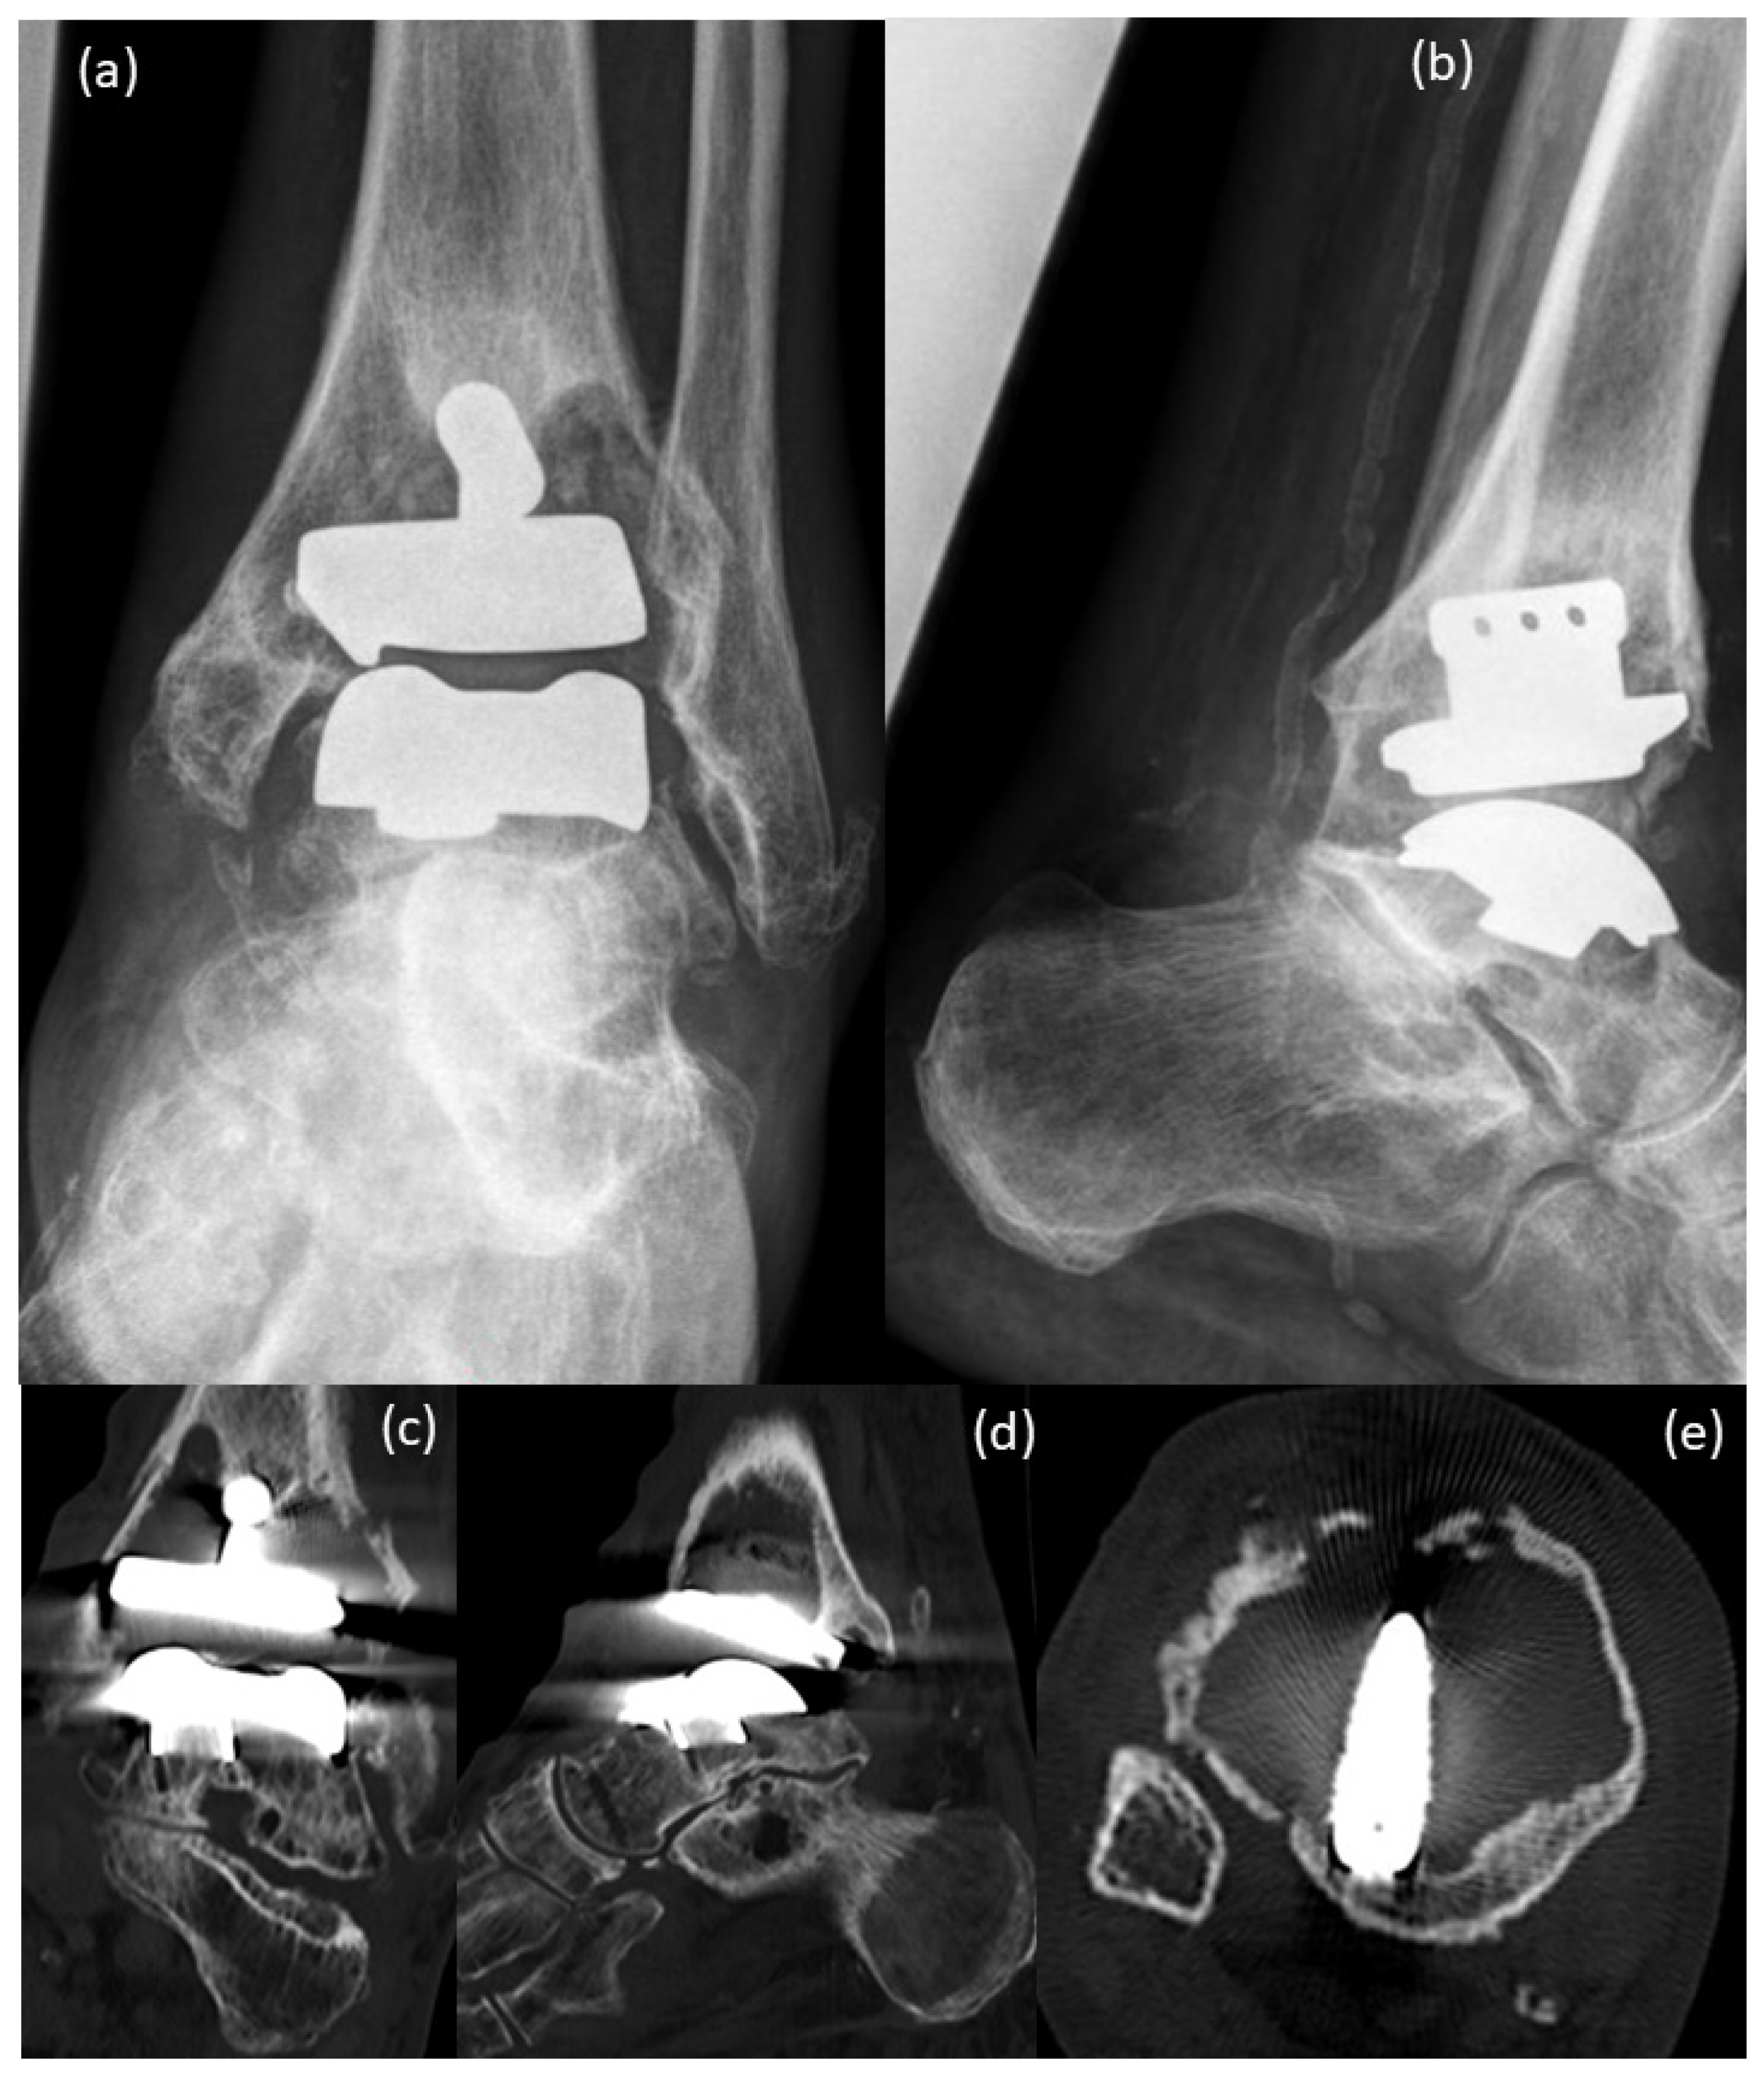

2. Case Presentation

3. Surgical Procedure

4. Postoperative Rehabilitation

5. Results